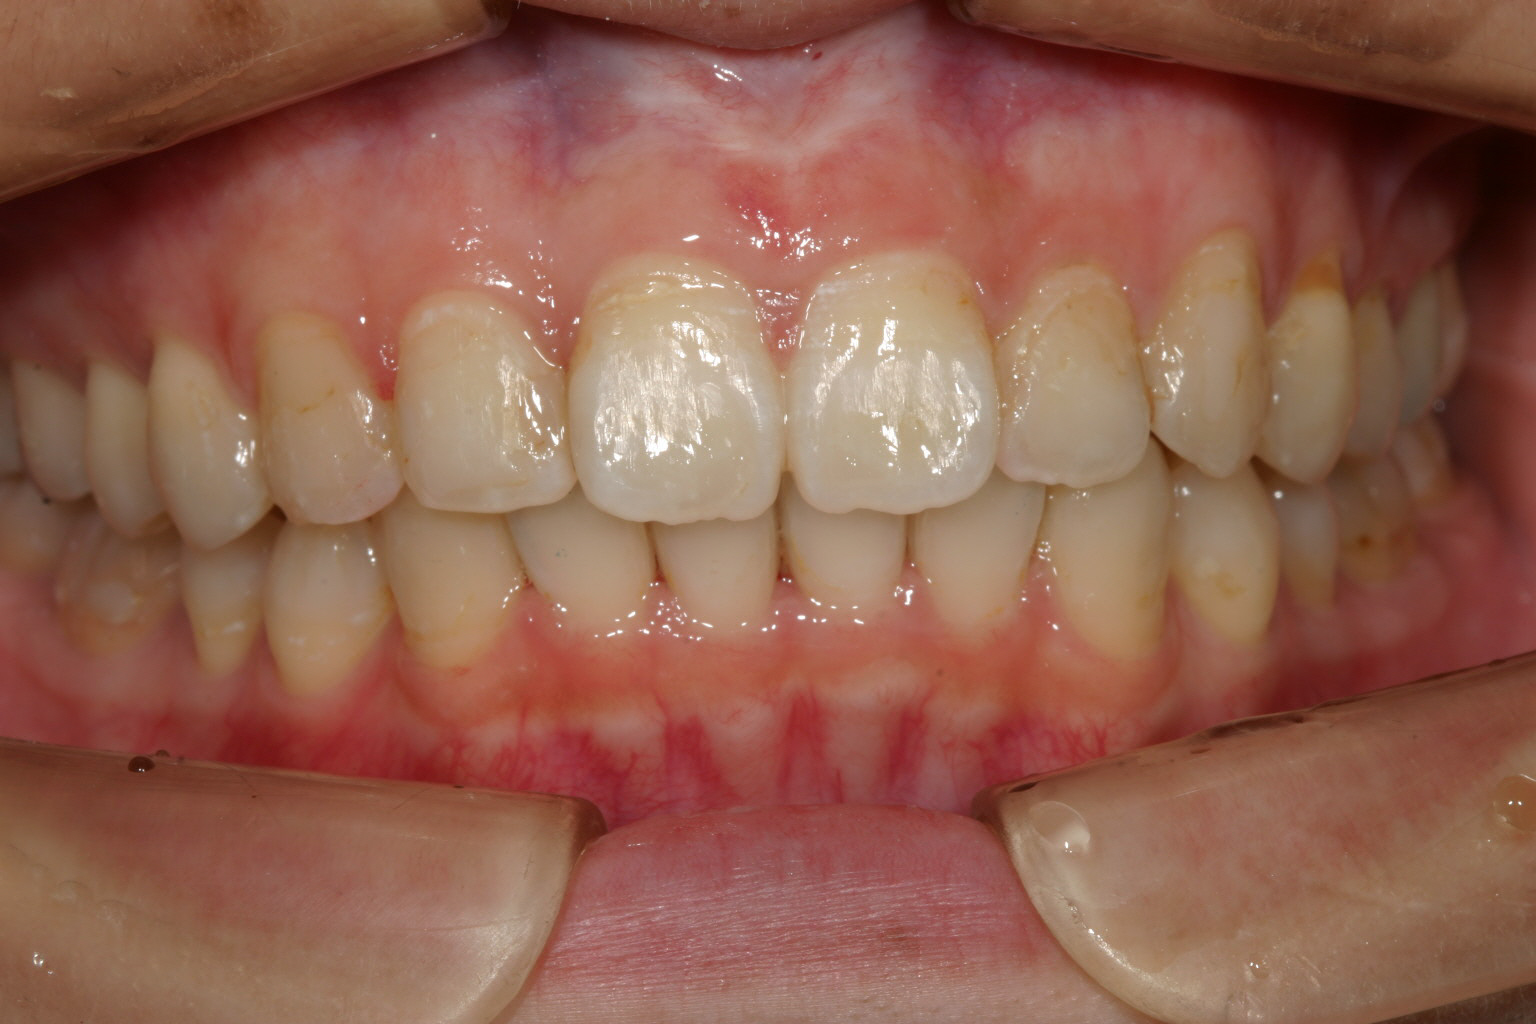

一生懸命インビザライン頑張って頂いたお陰で綺麗に改善致しました。

凄く綺麗に改善しました。 これは100点満点です。

大変綺麗に改善しました翼状捻転症例です。